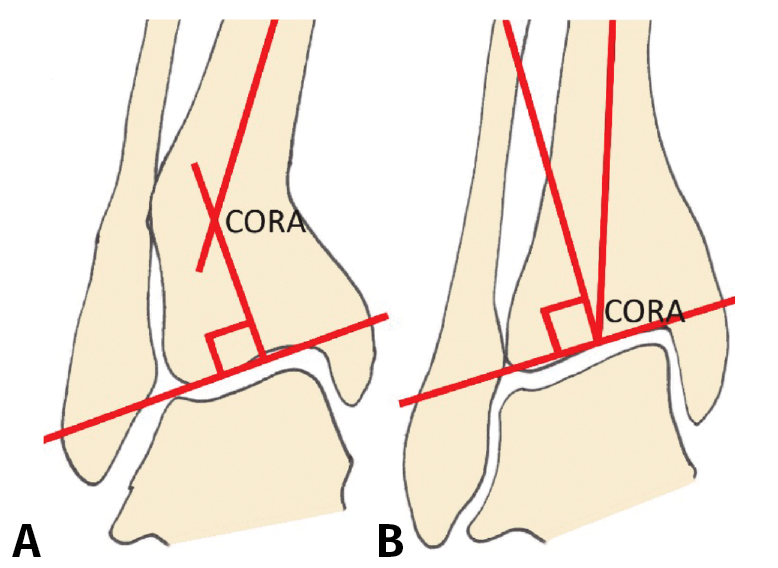

Debe incluir la radiología convencional (siempre en carga) dorsoplantar y lateral de ambos pies, anteroposterior y lateral del tobillo y la proyección de Saltzman. En el caso de haber apreciado deformidades en el miembro, solicitaremos también ambas extremidades completas. En el plano sagital (Figura 1), mediremos el ángulo tibial distal anterior (ADTA, por sus siglas en inglés). Este está formado por el eje mecánico de la tibia y la línea articular, y mide 80 ± 3° en la extremidad normal. Un aumento del ADTA representa una deformidad en recurvatum. En el plano coronal (Figura 1), se valora el ángulo tibial distal lateral (LDTA, por sus siglas en inglés), el ángulo tibio-talar y la alineación calcáneo-tibial. El LDTA(34) está formado por la superficie tibial articular distal y el eje anatómico de la tibia, y mide 89 ± 3°. La alineación calcáneo-tibial (medida en la proyección de Saltzman) es muy útil para confirmar la presencia de deformidades en varo o valgo, así como para valorar la compensación de un LDTA anormal (la articulación subastragalina puede compensar hasta 15° de eversión y 30° de inversión). Si tenemos un ADTA o LDTA anormal (deformidad sagital o coronal), debemos medir el center of rotation of angulation (CORA). Es la intersección entre la línea mediodiafisaria y la línea que comienza en el centro de la articulación y perpendicular al anormal ADTA o LDTA. El CORA puede estar localizado en la línea articular o proximalmente (Figura 2).

Figura 2. Medición y determinación del center of rotation of angulation (CORA). A: CORA supramaleolar; B: CORA en la articulación.